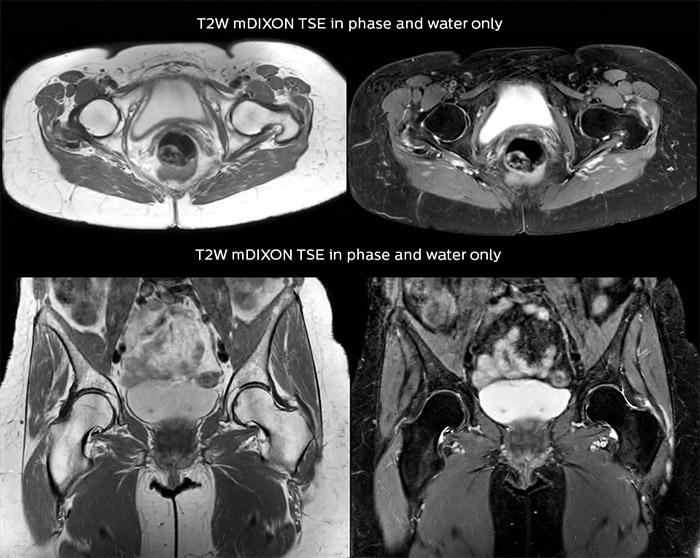

“Other examples in bone are the signal description of a necrotic fragment in osteonecrosis, the signal description of tumoral matrix that has different components (necrosis, hemorrhage, cartilage, bone formation). These are all possible thanks to in-phase and water images from a single mDIXON acquisition.”

“mDIXON TSE sequences allow simultaneous characterization of morphological changes from the in-phase T2-weighted images and visualization of edematous changes, thanks to the water T2-weighted images from the same acquisition. Anatomical and morphological considerations could be a partial or complete ligament tear, a bony avulsion or hematoma.”